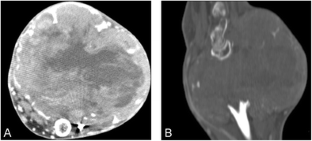

Fig. 3